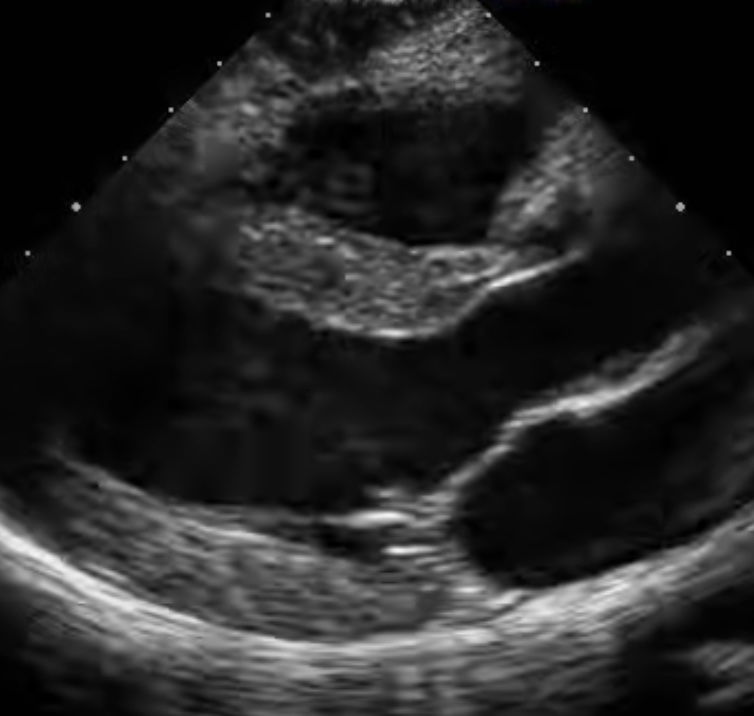

Ultrasound images of your heart are taken to assess cardiac function